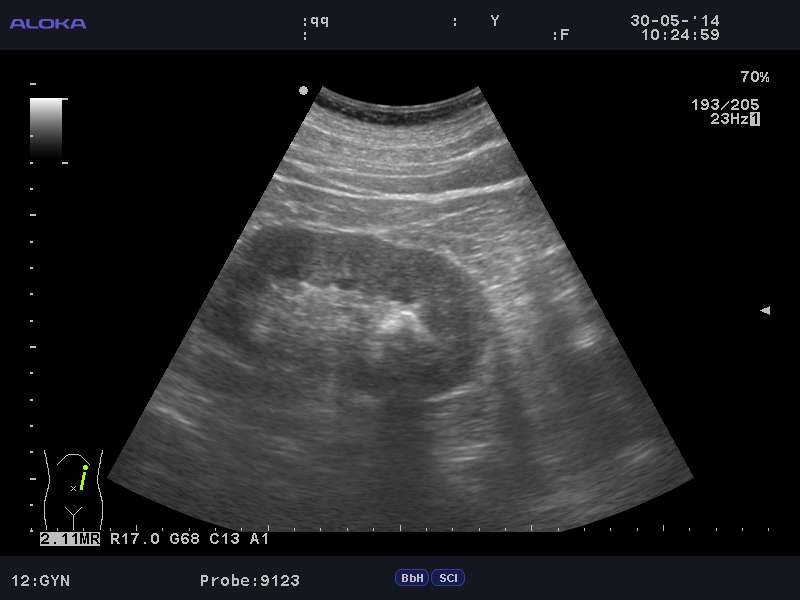

Камень верхней чашки левой почки

Мужчина средних лет